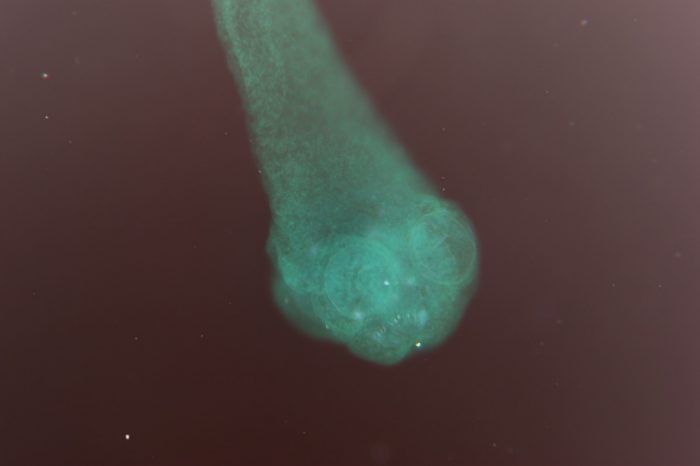

Морфология цепня не отличается от других ленточных червей. Карликовый цепень имеет следующую структуру:

- Длина не превышает 50 мм, ширина 1 мм.

- Тело представляет собой цепочку из множества повторяющихся члеников.

- Передняя часть червя является головой и имеет шейку.

- Голова оснащена четырьмя щелевидными присосками с выдвижным хоботком между ними.

- Хоботок по всей длине имеет 30-35 крючков для крепления на слизистой оболочке кишечника.

- Нервный ганглий находится в голове, от него идут сенсорные и хеморецепторные нервные волокна, простирающиеся по всему телу гельминта.